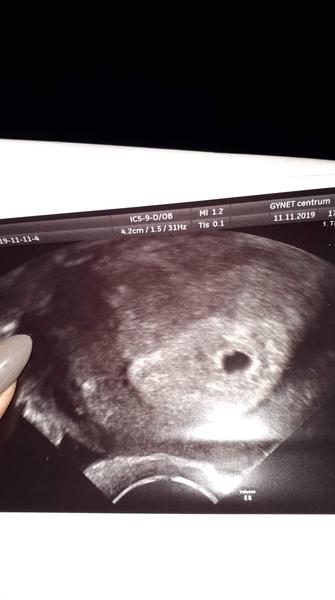

V 5. tt je vidět pouze gestační váček

ráda bych se s vámi pobavila o mé dnešní zkušenosti. Byla jsem u Dr. na ultrazvuku. Při minulé návštěvě(pouze potvrzení těhu) mi Dr. spočítala, že je to cca 5.tt podle poslední menstruace 22.7. a pozvala mě na dnešek. Při první návštěvě 23.8. mi potvrdila těhu pouze díky vysoké sliznici + 4 pozitivní testy(čárka postupně sílila) Dnes na mě během vaginálního utz vyrukovala s tím, že se jí to nelíbí a jde tedy nejspíš o zamlklé těhu, protože vidí pouze gestační váček a v 7.tt už by měla vidět srdíčko :( Začala už mluvit o revizi, takže mě samozřejmě totálně rozhodila. Myslím, že špatně odhadla délku těhu, teda spíš v to doufám. Myslím, že když ovulace byla cca 7.8. odpovídalo by to až teď tomu 5.tt. Udělala mi ještě test na hcg a to bylo cca 19 000. Dr. mi teď ještě volala, že se tedy nejspíš spletla v termínu a že bude snad všechno v pořádku. V neděli letíme na dovču, tak jsem z toho všeho nešťastná :(